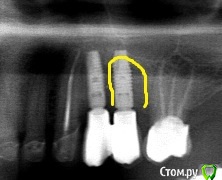

Тимур86 Опубликовано 15 октября, 2019 Поделиться Опубликовано 15 октября, 2019 (изменено) Вот такую убыль костной такни получили через 1.5 года после протезирования...Астра 4.0,костной пластики в области 25 не было,кости было хоть отбавляй,рг после протезирования идеальный,соматических заболеваний (вроде) нету. Откуда такая убыль за столь короткий срок? Изменено 15 октября, 2019 пользователем Тимур86 Ссылка на комментарий

gum Опубликовано 16 октября, 2019 Поделиться Опубликовано 16 октября, 2019 На снимке до есть в кости вкрапления рентгеноконтрастного материала (пломбировочный похоже) в области 25, возможно это явилось причиной Ссылка на комментарий

red_butler Опубликовано 16 октября, 2019 Поделиться Опубликовано 16 октября, 2019 А что это? Не цемент? Ссылка на комментарий

Тимур86 Опубликовано 16 октября, 2019 Автор Поделиться Опубликовано 16 октября, 2019 Нет, там винтовая фиксация. Это скорее всего биоос, оставшийся после одномоментной имплантации 24 Ссылка на комментарий